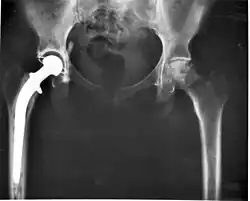

Medical implants

An implant is a kind of medical device made to replace and act as a missing biological structure (as compared with a transplant, which indicates transplanted biomedical tissue). The surface of implants that contact the body might be made of a biomedical material such as titanium, silicone or apatite depending on what is the most functional. In some cases, implants contain electronics, e.g. artificial pacemakers and cochlear implants. Some implants are bioactive, such as subcutaneous drug delivery devices in the form of implantable pills or drug-eluting stents.

Implants, such as artificial hip joints, are generally extensively regulated due to the invasive nature of such devices.

• Class III devices generally require premarket approval (PMA) or premarket notification (510k), a scientific review to ensure the device's safety and effectiveness, in addition to the general controls of Class I. Examples include replacement heart valves, hip and knee joint implants, silicone gel-filled breast implants, implanted cerebellar stimulators, implantable pacemaker pulse generators and endosseous (intra-bone) implants.